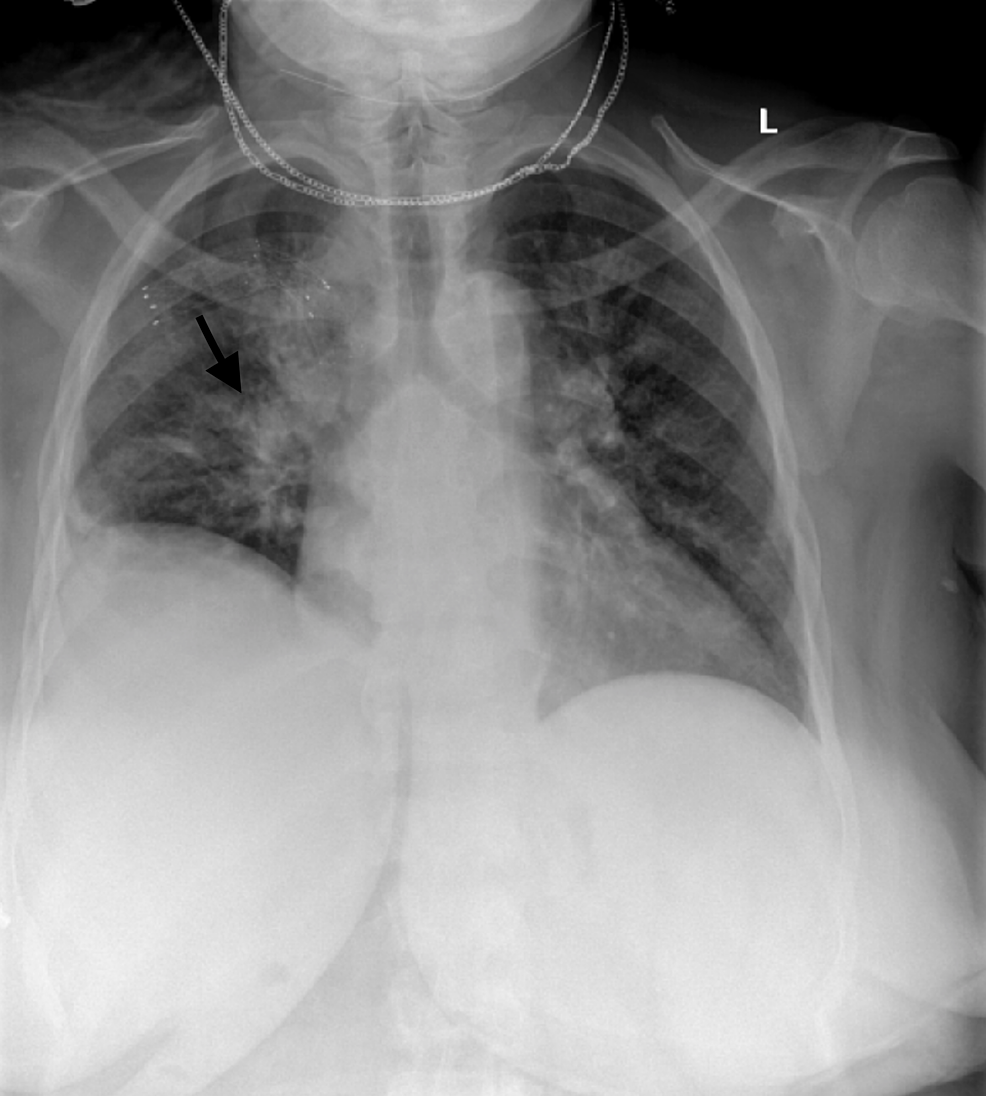

Chest radiograph on the day of ER visit demonstrating bilateral Waxing And Waning Infiltrates These are most commonly found affecting the lung bases, this pattern is. He did not report any hemoptysis or chest pain, but reported. Medical conditions characterized by waxing and waning often exhibit a cyclic pattern. 23 infiltrates may be migratory, have a. Waxing and waning fevers, fatigue, productive cough, chills, and night sweats. They may resolve spontaneously, wax and wane. Waxing And Waning Infiltrates.